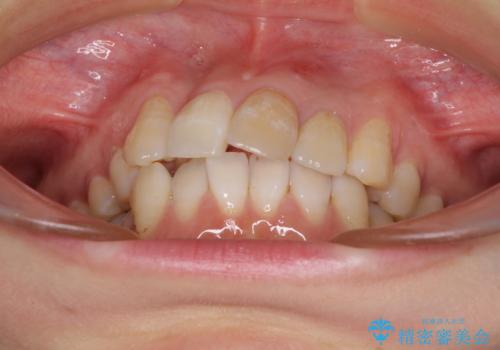

- 重なった前歯を邪魔に感じ、汚れも溜まりやすいことを気にして来院された患者様です。

右上前から2番目の歯が内側に転位しているため、上顎の正中は右にずれていました。